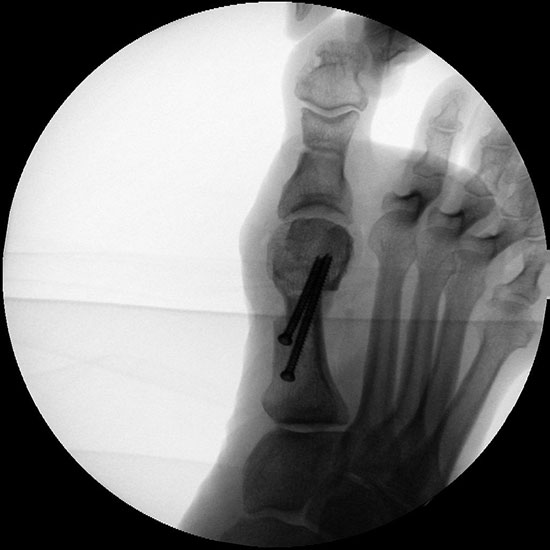

• Stabilität durch eine Osteosynthese analog zum offenen Vorgehen.

• Korrekturpotential größer als beim offenen Chevron, da die Gelenkkapsel als stabilisierendes Element erhalten bleibt und über eine trikortikale Osteosynthese mit zwei kanülierten Schrauben eine Verschiebung bis ca. 80% des Metatarsaledurchmessers möglich ist (Abb. 1).